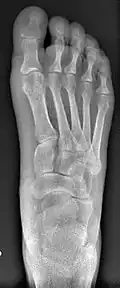

- Second metatarsal stress fracture (Fig. 5)

- Over-correction (Fig. 6)